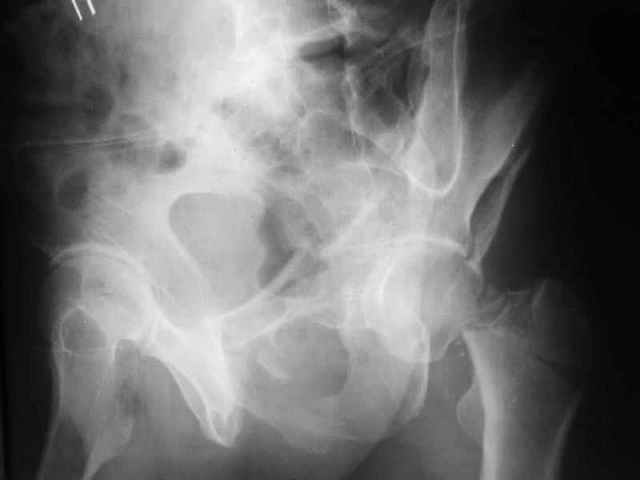

Два месяца нагрузки без костылей 19/12/03

|

Еще месяц 20/02/04

Больной 18 мая 2003 года в автоаварии получил перелом левой вертлужной впадины, вывих бедра. Госпитализирован в один из стационаров области.Вывих вправлен. В последствии бедро вывихивалось еще дважды. На консультацию был представлен снимок от 19.05.03г., больной переведен к нам 3.06.03г. Снимок при поступлении - перелом впадины, задне-верхний вывих бедра. 05.06.2003 г. выполнено открытое вправление вывиха левого бедра и остеосинтез стенки вертлужной впадины двумя винтами. Послеоперационный период без осложнений. Объем движений в левом тазобедренном суставе восстановился полностью. Выписан на амбулаторное лечение в удовлетворительном состоянии с рекомендациями 3 месяца ходить на костылях без нагрузки на оперированную конечность. На контрольных рентгенограммах левого тазобедренного сустава 13.10.2003 г. - признаки консолидации перелома; плотность, форма головки и состояние суставных поверхностей удовлетворительные. Разрешена дозированная осевая нагрузка, на конечность с использованием дополнительной опоры. 19.12.2003 г. больной обратился с жалобами на боли в левом тазобедренном суставе. На рентгенограммах левого тазобедренного сустава 19.12.2003 г., 20.02.04г. - асептичекий некроз головки бедра. 5.04.04г. - эндопротез. Сейчас ходит без трости, не хромает. Особенность эндопротезирования - при удалении винтов прослежена линия перелома заднего края впадины и предложено установить чашку несколько меньшего диаметра, чтобы она была покрыта несломанной частью.